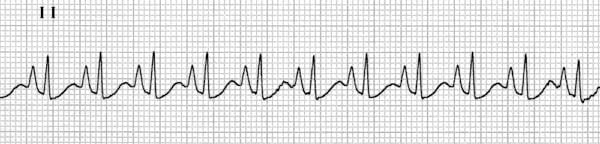

Ventricular Tachycardia (VT)

Be aware that VT without a pulse is a shockable cardiac arrest rhythm. Treat accordingly to the ALS algorithm, see this article.

However, VT can also be with a pulse. In that case, treat accordingly to the peri-arrest tachycardia algorithm, see this article.

VT is a tachyarrhythmia that originates from the ventricles, defined by ≥3 consecutive PVCs at a rate of >100 bpm

- VT occurs when abnormal electrical impulses arise from ventricular tissue, either due to reentry, abnormal automaticity, or triggered activity

- The classic cause is a re-entrant circuit that forms around scarred myocardium (e.g. in MI), leading to rapid activation of the ventricles

Classification of VTs:

- Sustained vs non-sustained

- Sustained VT: lasts >30 sec

- Non-sustained VT: lasts <30 sec (3-30 consecutive PVCs)

- Monomorphic vs polymorphic

- Monomorphic VT: all QRS have the same shape (as they originate from the same ventricular focus / circuit)

- Polymorphic VT: there are >1 QRS shapes (as they originate from different ventricular foci / circuits)

Torsade de pointes (TdP) is a specific type of polymorphic VT that occurs in the context of QTc prolongation.

ECG features:

- Regular, broad complex tachycardia is VT until proven otherwise (at least for medical students and non-specialists…)

- There are specific ECG features that suggest VT over other causes, but they are of excessive detail

- TdP has a varying QRS morphology and the QRS complexes appear to be “twisting” around the isoelectric line

This is an ECG of monomorphic VT. Note the very regular, broad complex tachycardia and the same QRS morphology throughout.

https://litfl.com/ventricular-tachycardia-ecg-library/

© Life in the Fast Lane. Licensed under CC BY-NC 4.0

This is an ECG of polymorphic VT (specifically, Torsades de Pointes – a type of polymorphic VT). The varying QRS morphology can be appreciated, with the characteristic morphology of QRS complexes “twisting” around the isoelectric line.

https://litfl.com/torsades-de-pointes-ecg-library/

© Life in the Fast Lane. Licensed under CC BY-NC 4.0